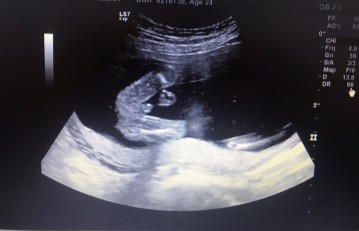

20+1แล้วจร้ายังไม่ได้ซาวด์เพศ แม่ๆคนไหนซาวด์เพศแล้วบ้างได้ ช. หรือ ญ. กี่สัปดาห์กันแล้วค่ะ